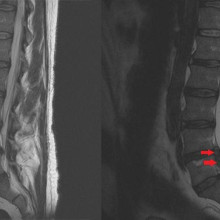

Study suggests that surgery may be superior treatment for chronic sciatica

In a randomized controlled trial, surgery was found to be superior to non-operative therapy in the treatment of chronic sciatica. Chronic sciatica can be caused by a disc herniation which compresses a nerve in the lumbar spine causing pain from the lower back to the leg. The primary treatment options for sciatica are surgery or non-operative care. Researchers conducted this study to test if a surgical treatment called microdiscectomy results in better patient outcomes for those with chronic sciatica compared to non-operative care. Read more.